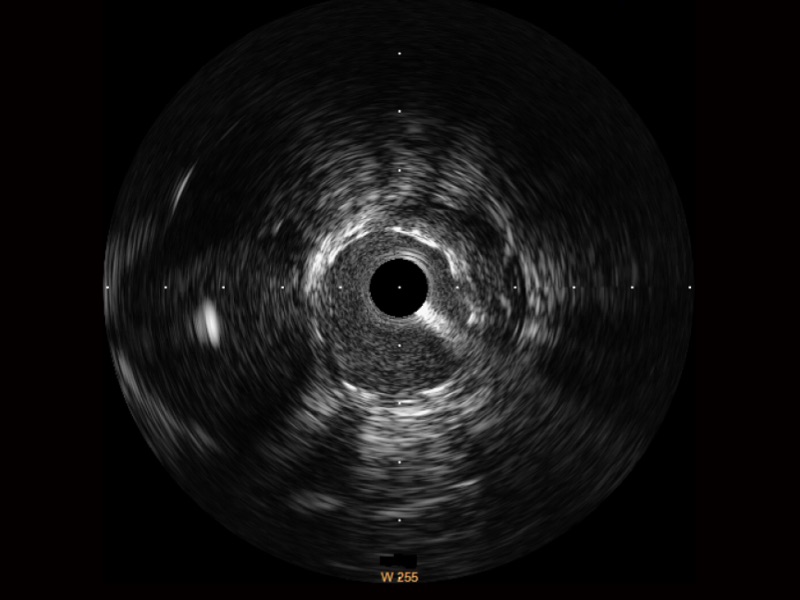

乐玩lewin国际宽频IVUS图像

传统IVUS图像

对比传统IVUS导管成像,乐玩lewin国际宽频IVUS图像的近场支架梁显影更细腻,远场中膜外血管仍清晰可辨,兼顾远中近,兼顾分辨力与穿透深度